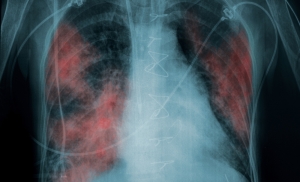

ХОБЛ

Интерстициальные заболевания легких